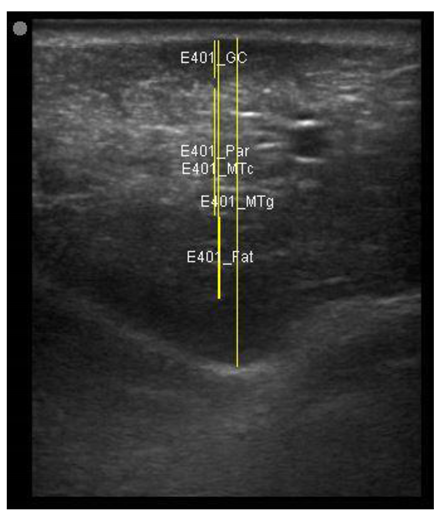

A minimum of three images were taken from each udder half. Images included the gland cistern, mammary parenchyma, putative fat pad and the boundary between the mammary gland and the abdominal wall. One image of suitable resolution per udder half, where all structures were identifiable and present was selected for image processing [27]. Udder halves with an udder palpation score of 4 or 5 (Table 1) at a specific time point (P107, L29 or L100) were considered “abnormal” [23] and were not included in the image selection (heavy: 1 ewe with 1 half and control: 2 ewes with 1 half each).

The image processing was undertaken using ImageJ software [28] as used by Abràmoff et al. [29]. The scales between pixels and millimetres were calculated based on the number of pixels, the scanning depth (mm), and the transducer width (mm) (Figure 4). This method relies on the ability of the operator to interpret and identify lines on the images. To standardize the assessment compartment depth, drawing templates were created for each time point as used by Molenaar et al. [30] and included four representative images from four different yearling ewes with and without the lines drawn for each compartment (Appendix A). The total depth of mammary gland conservative (MTc) was the smallest likely demarcation (abdominal wall) of the mammary gland (Figure 5a), and total depth of the mammary gland generous (MTg) was the largest likely demarcation of the mammary gland visible on the image [30] (Figure 5a). The MTc, MTg, fat pad (FP), parenchyma (PAR), and gland cistern (GC) depths were estimated at the deepest point for each sub-compartment, excluding the skin layers, using the straight tracer (Figure 5a) and were expressed in millimetres.

Figure 5.

(a) Demonstration of delimitations of the mammary total depth conservative (MTc) and generous (MTg), mammary gland cistern (GC), parenchyma (PAR) and the fat pad (FP) and (b) Demonstration of randomly positioning of regions of interest (1, 2, 3) in the parenchyma.